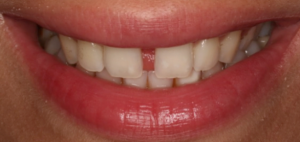

A midline diasetma or gap can be present for many...